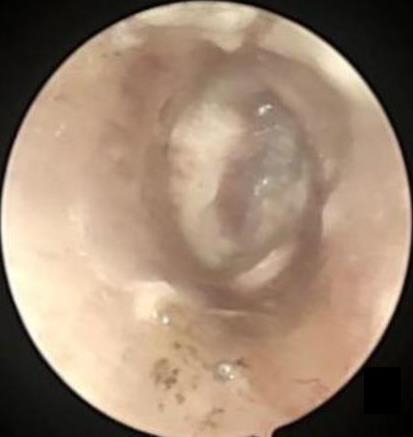

• 医用生物蛋白胶应用于耳内镜下鼓膜修补术的临床疗效

摘要:目的 分析医用生物蛋白胶应用于耳内镜下鼓膜修补术的临床疗效。方法 回顾性分析2022年10月-2023年10月该院收治的60例单纯鼓膜穿孔患者的临床资料,根据手术方法不同,将患者分为研究组和对照组,各30例。研究组术中使用医用生物蛋白胶粘合残余鼓膜和修补材料;对照组术中采用明胶海绵覆盖修补鼓膜。观察两组患者术后的鼓膜愈合情况(鼓膜愈合率、愈合时间、干耳时间和外耳道上下径)和并发症发生情况;于手术前后,采用纯音测听法(500、1 000、2 000、4 000 Hz),测量两组患者气导阈值,观察听力改善程度;采用视觉模拟评分法(VAS)评分,评估患者术后疼痛程度。结果 两组患者术后鼓膜愈合率、愈合时间、外耳道上下径和并发症发生率比较,差异均无统计学意义(P > 0.05)。研究组术后平均气导听阈明显低于对照组,差异有统计学意义(P < 0.05)。研究组术后干耳时间短于对照组,术后第1天疼痛VAS评分明显低于对照组,差异均有统计学意义(P < 0.05)。结论 医用生物蛋白胶应用于耳内镜下鼓膜修补术,可有效地降低气导听阈,缩短干耳时间,减轻患者疼痛,且不增加并发症发生率,值得临床推广应用。